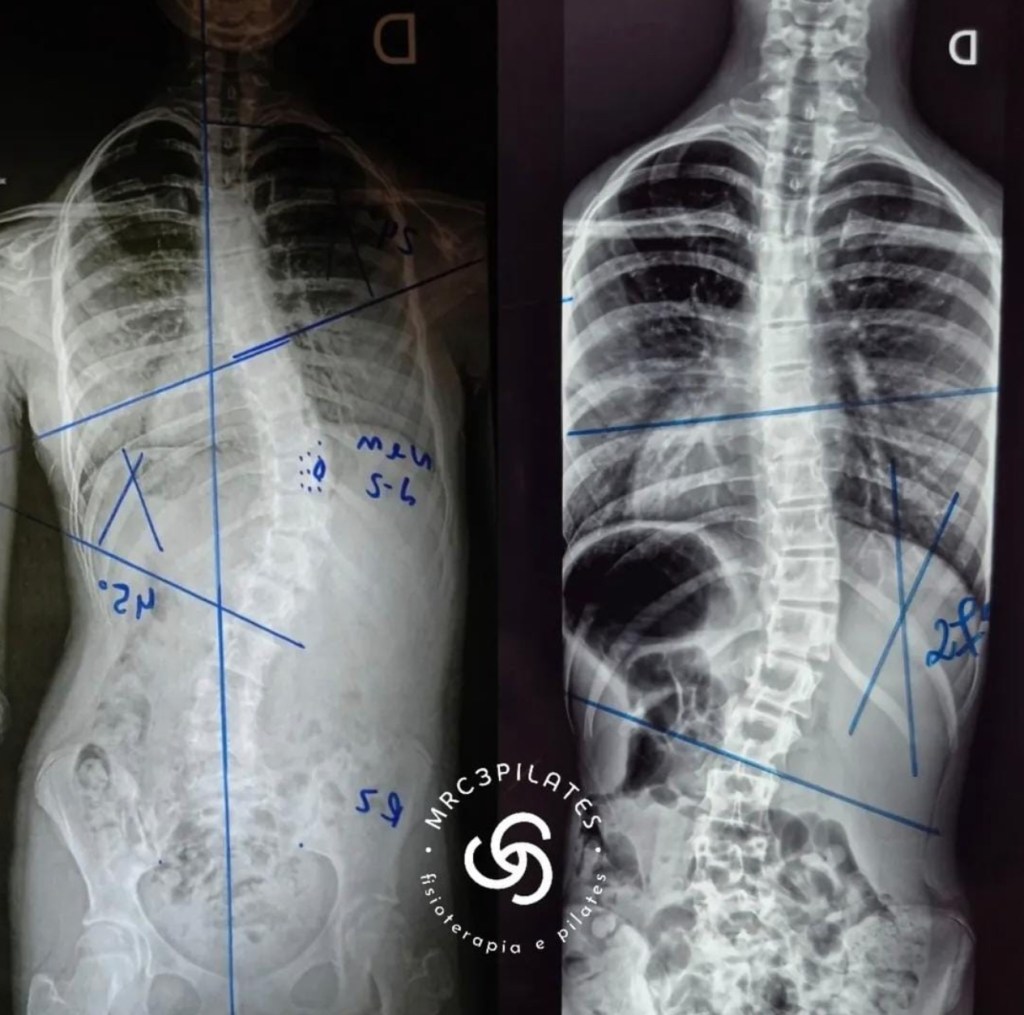

Tratamento especializado para escoliose com abordagem moderna e eficaz. Trabalhamos com o método S4D e coletes personalizados, que combinam exercícios específicos com correção postural ativa. Nossos protocolos são baseados em estudos internacionais e focados na melhora real da curvatura e qualidade de vida do paciente. Apresentamos comparações visuais de resultados reais e acompanhamento completo.

Resultado de 6 meses de tratamento com exercícios específicos e colete S4D